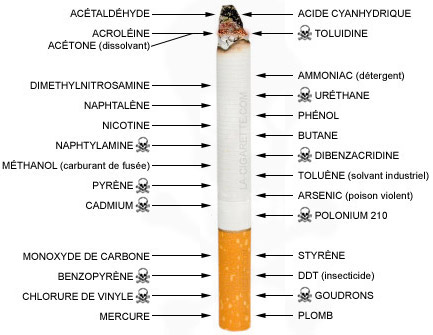

- Cosa contiene una sigaretta?

I componenti contrassegnati con il Teschio sono quelli che causano maggior pericolo di morte!